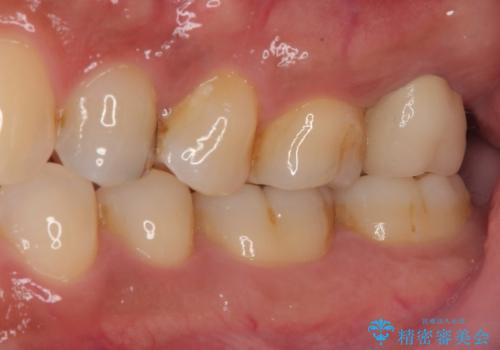

初回治療後には速やかに痛みが改善され、非常に大きかったレントゲンでの骨透過像も改善されました。